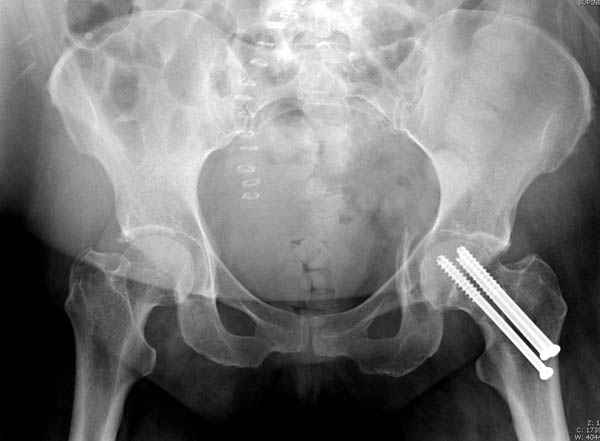

Уважаемые коллеги! С прошедшеми Вас праздниками. Теперь ближе к трудовым будням. Поступила 16 летняя девушка неделю назад. Механизм травмы падение с 5 этажа. Краткий диагноз:закрытый перелом левой ключицы, левого плеча, закрытый вертикально и ротационно нестабильный перелом костей таза:закрытый перелом левой подвздошной кости, переломы лонной кости справа, перелом обоих колонн вертлужной впадины слева;субкапитальный перелом шейки левой бедренной кости со смещением. По тактике лечения таза возникли следующие вопросы: 1. С чего начать - фиксации переломов вертлужной впадины или устранения деформаций таза? 2. Надо ли фиксировать шейку или фиксировать бедро в аппарате вместе с тазом, а после сращения таза планировать ТЭП ТБС? Если имеются еще какие подводные камни, будем рады выслушать.Спасибо.

У нас в таких случаях однозначно сделали бы остеосинтез Ш.Б. компрессирующими винтами, затем ЗВО таза, однозначно с дополнительной фиксацией в этом же аппарате бедра с разгрузкой тазобедренного сустава

В положении на спине подвздошным и надлобковым доступом восстанавливается тазовое кольцо, фиксация пластинами. При хорошей репозиции может улучшиться конгруэнтность в суставе.

Затем, если положение хорошее, закрытый остеосинтез шейки винтами.

Если нет - в положении на боку, синтез задней колонны из наружно-латерального доступа и синтез головки винтами, но уже под визуальным контролем.

На картинке подобный случай, только без шейки, сделано через месяц или полтора после травмы.